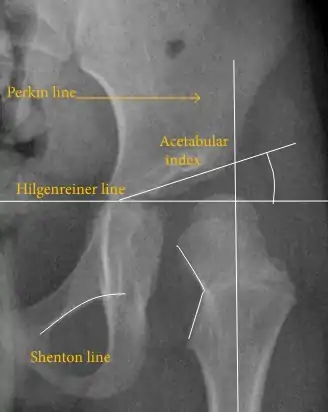

The most useful lines and angles that can be drawn in the pediatric pelvis assessing hip dysplasia are as follows:[43] Different measurements are used in adults.[43]